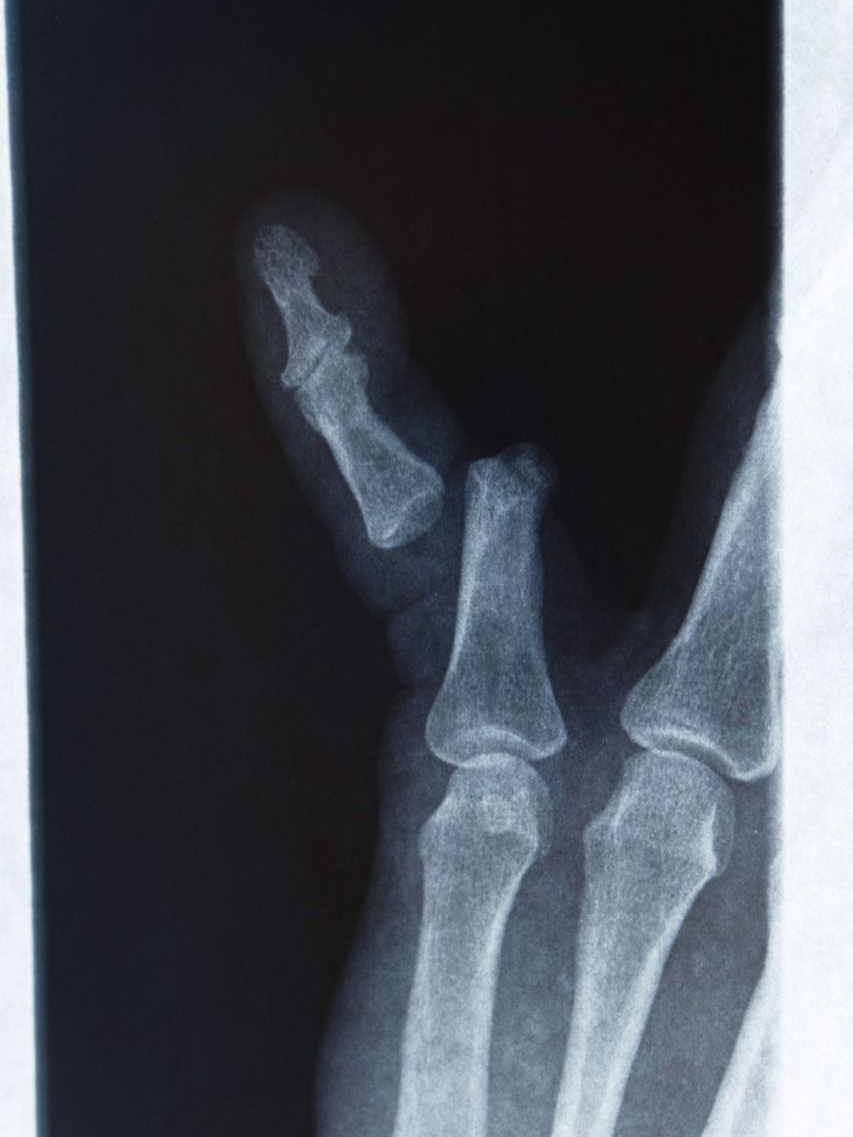

비전위성 골절(뼈가 어긋나지 않은 경우)은 대체로 3~4주 내에 유합이 일어나며, 스플린트나 테이핑으로 충분히 치료가 가능합니다. 반면 전위성 골절은 뼈가 틀어진 상태로 남으면 손가락이 휘거나 굽힘 제한이 생길 수 있어, 경우에 따라 핀 고정(수술)이 필요합니다. 수술을 시행한 경우에는 6~8주 정도의 회복 기간이 필요하며, 이후 관절 가동 범위를 회복하기 위한 물리치료가 필수입니다.

손가락에 금이 갔을 때 무조건 깁스를 해야 하는 것은 아닙니다. 뼈가 어긋나지 않은 단순 골절이라면 스플린트나 버디 테이핑만으로도 충분히 치료가 가능합니다. 깁스는 뼈가 크게 전위되었거나, 여러 조각으로 부서졌을 때, 혹은 골절선이 관절면을 침범해 안정적인 고정이 필요한 경우에만 시행합니다.